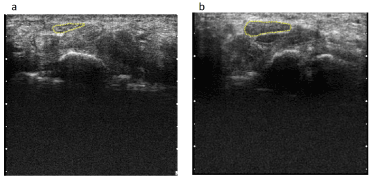

Figure 3. Ultrasonographic images of a healthy individual and a patient with carpal tunnel syndrome (CTS) in the resting position

a: Healthy person’s left hand

b: Patient’s left hand

The dotted yellow line indicates the border of the median nerve.